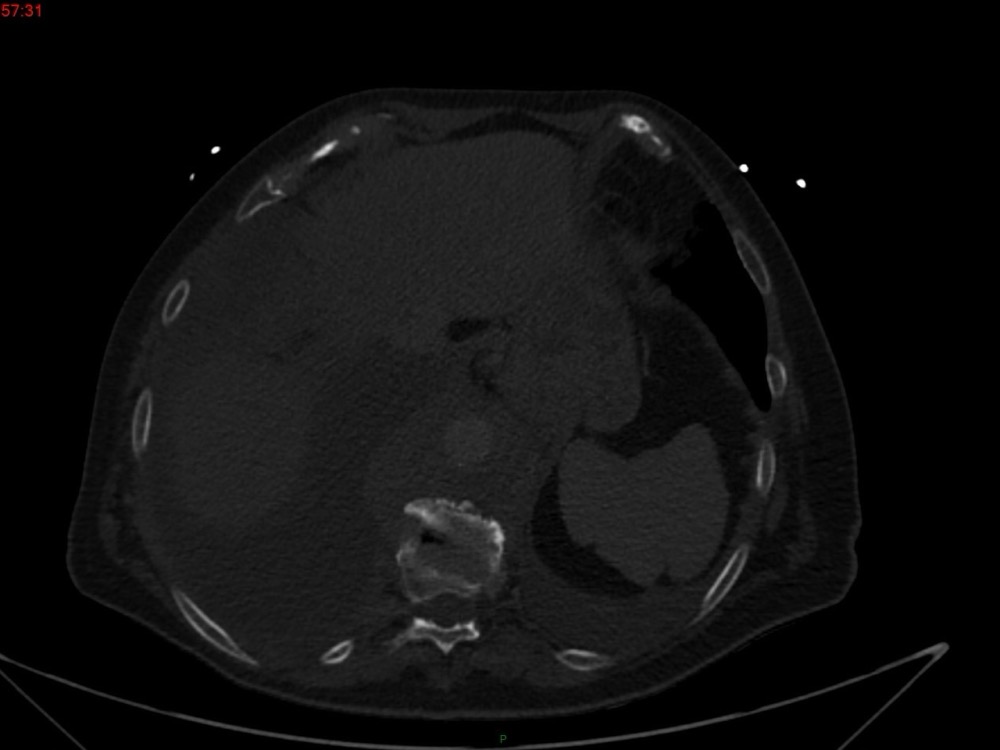

Marie Pauline Talabard 11/01/2023